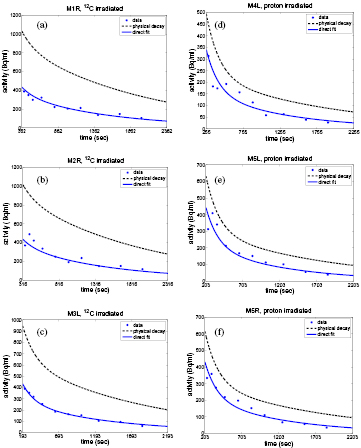

The results for the washout parameters are reported in table 3. The model of continuous irradiation is used for the reported results. All of the selected 12C mice data sets were best fitted by an unconstrained two component fit. Fits that converged to very high Ts are marked by >100 000 and >18 000 in one case. The data sets of mice irradiated with protons were best fitted by an unconstrained one component fit. They gave physically inconsistent values when fitted with an unconstrained two component fit (negative Ms/Mm), while the constrained two component fit converged to the listed one component fit. The successive fit proved to be inconclusive due to the decrease in statistics when starting the fit at least 500 s after irradiation, as required to suppress the medium component. The result of the collective fit gave instead satisfactory results (figure 4) and its comparison to the average and one standard deviation from the separate fits of the individual mice data sets can be seen in table 4.

Figure 4. Results of the collective fit plotted against time with respect to the end of irradiation with 12C-ions (a, b, c) and protons (d, e, f) (see table 1). The physical decay calculated according to section 2.3.3 is shown as a dashed line for comparison. As the method of the collective fit is used, the curves do not give the optimum fit for the individual data points. Still the general time course is well reproduced.

The comparison of the dynamic with the static PET gave very good consistency for almost all living mice, except mouse 4l,a. Here, the deviation was higher with 6.4% (table 3), likely due to low counting statistics (see figure 4d).

All of the 12C data sets gave results with a very long Ts, whereas the Tm varied. While the data from mouse 1r and mouse 2r was relatively consistent in Tm, analysis of the mouse 3l data set yields a higher value. This could be due to an incorrect estimation of the 15O fraction in the fit of Aphys. Nevertheless, as can be seen in figure 4(c), the estimation from the collective fit also gives a good result for mouse 3l, when assuming a shorter half life of the medium component. The analysis of the data of all proton mice yielded a consistent value for Ts.